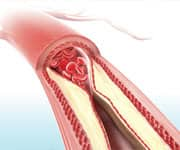

Despite all the advances in cholesterol-lowering medications and surgical interventions, atherosclerosis, coronary artery disease, heart attack, heart failure, stroke, and peripheral vascular disease remain the leading causes of death and disability in the United States.2,3

Further demonstration of Pycnogenol’s ability to slow or prevent the progression of cardiovascular disease comes from a 2014 study of people with atherosclerosis of the femoral (leg) or carotid (neck) arteries.5 Although these patients had not yet developed symptoms, they all had atherosclerotic plaques visible on ultrasound examination of their vessels. The patients were divided into several groups that included low-dose Pycnogenol (50 mg/day), higher-dose Pycnogenol (100 mg/day), aspirin, or a combination of Pycnogenol ( 100 mg/day) and aspirin.

In the groups that received either no Pycnogenol or just 50 mg/day, ultrasound evidence of progression (larger or more frequent plaques) was visible. In all groups receiving 100 mg/day Pycnogenol, progression was almost completely halted. The percentage of individual plaques that progressed to the dangerous and irreversible stage called “fibroatheroma” was less than 6% in subjects taking 100 mg/day Pycnogenol, but rose to 16.6% in those receiving aspirin-only, and went up to 21.3% in controls (receiving neither aspirin or Pycnogenol).5

Four-Step Creation Of Harmful Plaque7-11

- Oxidative stress leads to the oxidation of LDL particles that have accumulated within the inner lining of the arterial wall (endothelium).

- Oxidized LDL and damaged endothelial cells trigger an inflammatory response in which immune cells (monocytes/macrophages) are recruited.

- The recruited macrophages ingest oxidized LDL and transform into “foam cells,” which accumulate within the endothelium to form plaque.

- Muscle cells in the artery then proliferate and secrete fibrous elements to form a “cap” around the plaque.

The result is stiffening of the arteries and impeding blood delivery to vulnerable tissues across the body, potentially producing heart attacks, strokes, and other manifestations of cardiovascular disease.

Pycnogenol acts to slow or stop multiple stages in the domino effect leading to cardiovascular disease, with impressive clinical results.4-6